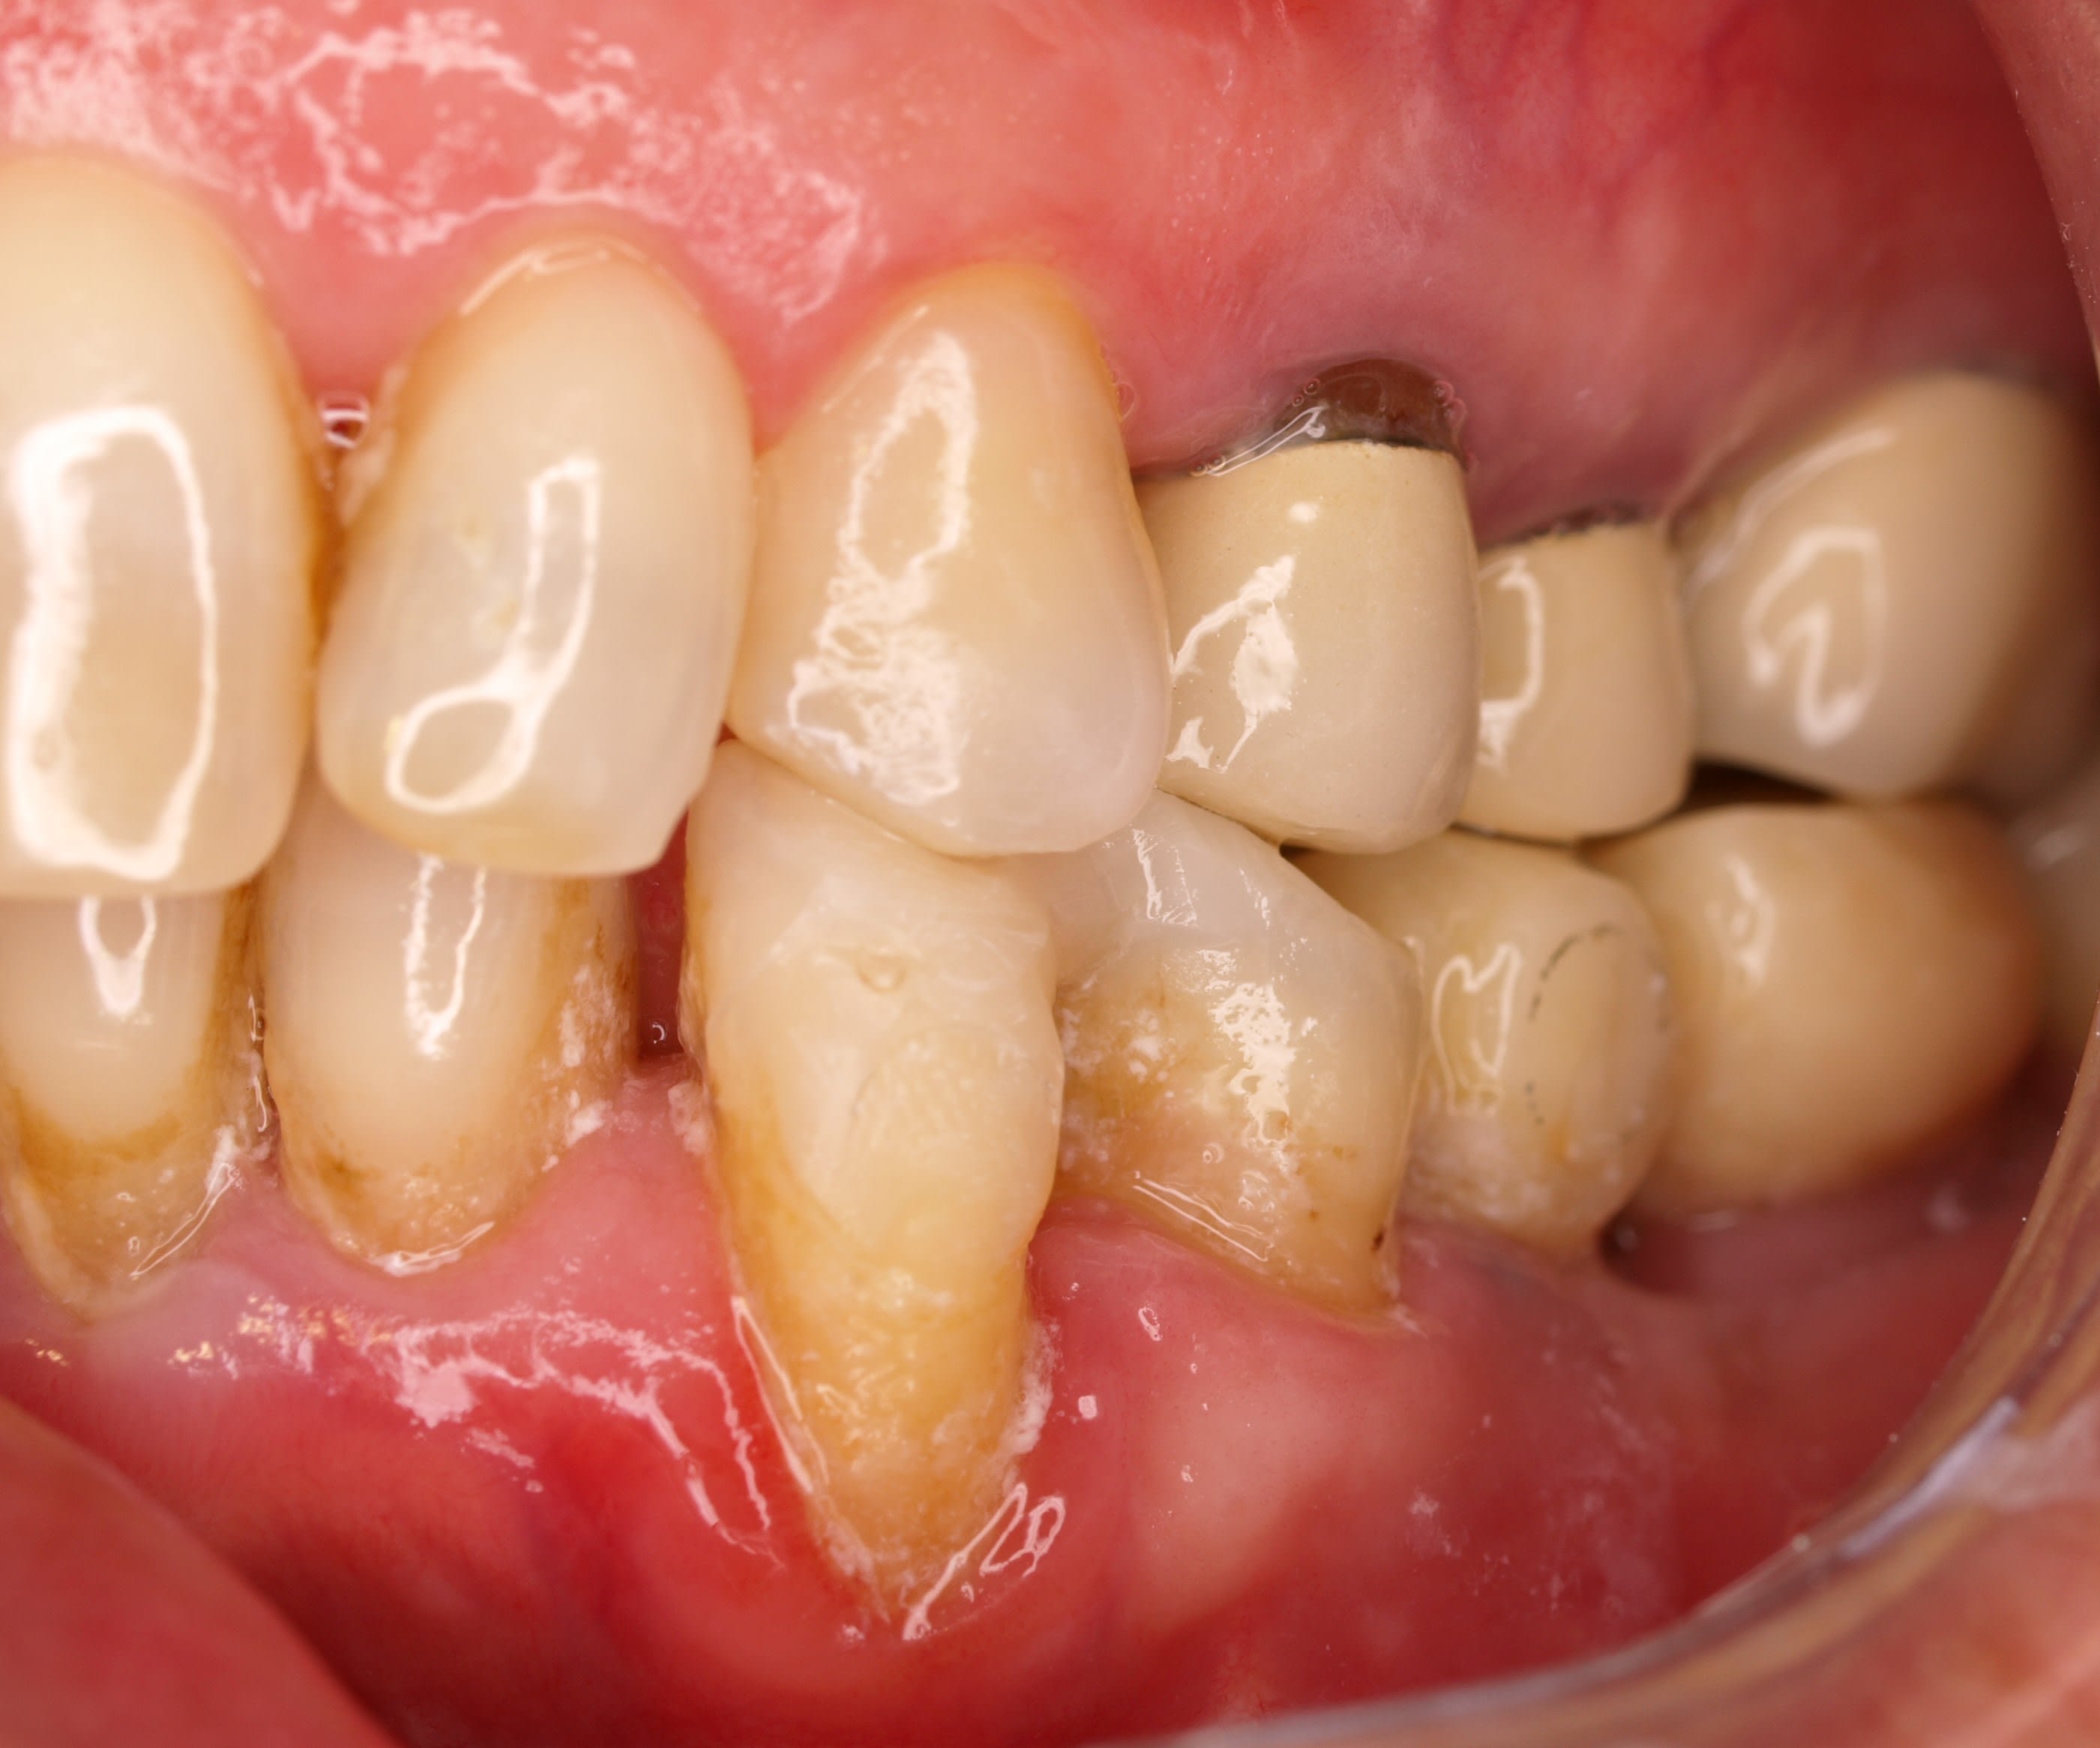

et là c est mardi passé , donc 8 ans apres et elle a donc 85 ans . j en profite pour lui refaire sa 26 .

et là il me vient 2 remarques qui sont flagrantes .

donc en attendant qu on en parle , vous pouvez commenter et critiquer ou pas ce serait avec plaisir .

et c' est quoi ces 2 remarques d après toi ?

8 bhzsyh - Eugenol

7 mzojmm - Eugenol

Y'a de la plaque partout, sauf sur tes cerams?

Les antérieures semblent avoir égressé et s'être lingualées, mais c'est presque l'évolution normale ça.

" Y'a de la plaque partout, sauf sur tes cerams? "

eh oui ç est la 1ere chose , et c est flagrant .surtout quand il n y a pas de metal , ici ce sont des @max

meme sur la 34 ou il y a une récession , ç est nickel .

alors tu me diras par exemple tel coté elle a mal au bras , et elle ne se brosse pas bien , ..., mais regarde la 24 pareil propre alors que le secteur 20 n est pas top

j ai tjs dit que la paro sans la prothese ç est du pipo en exagerant .